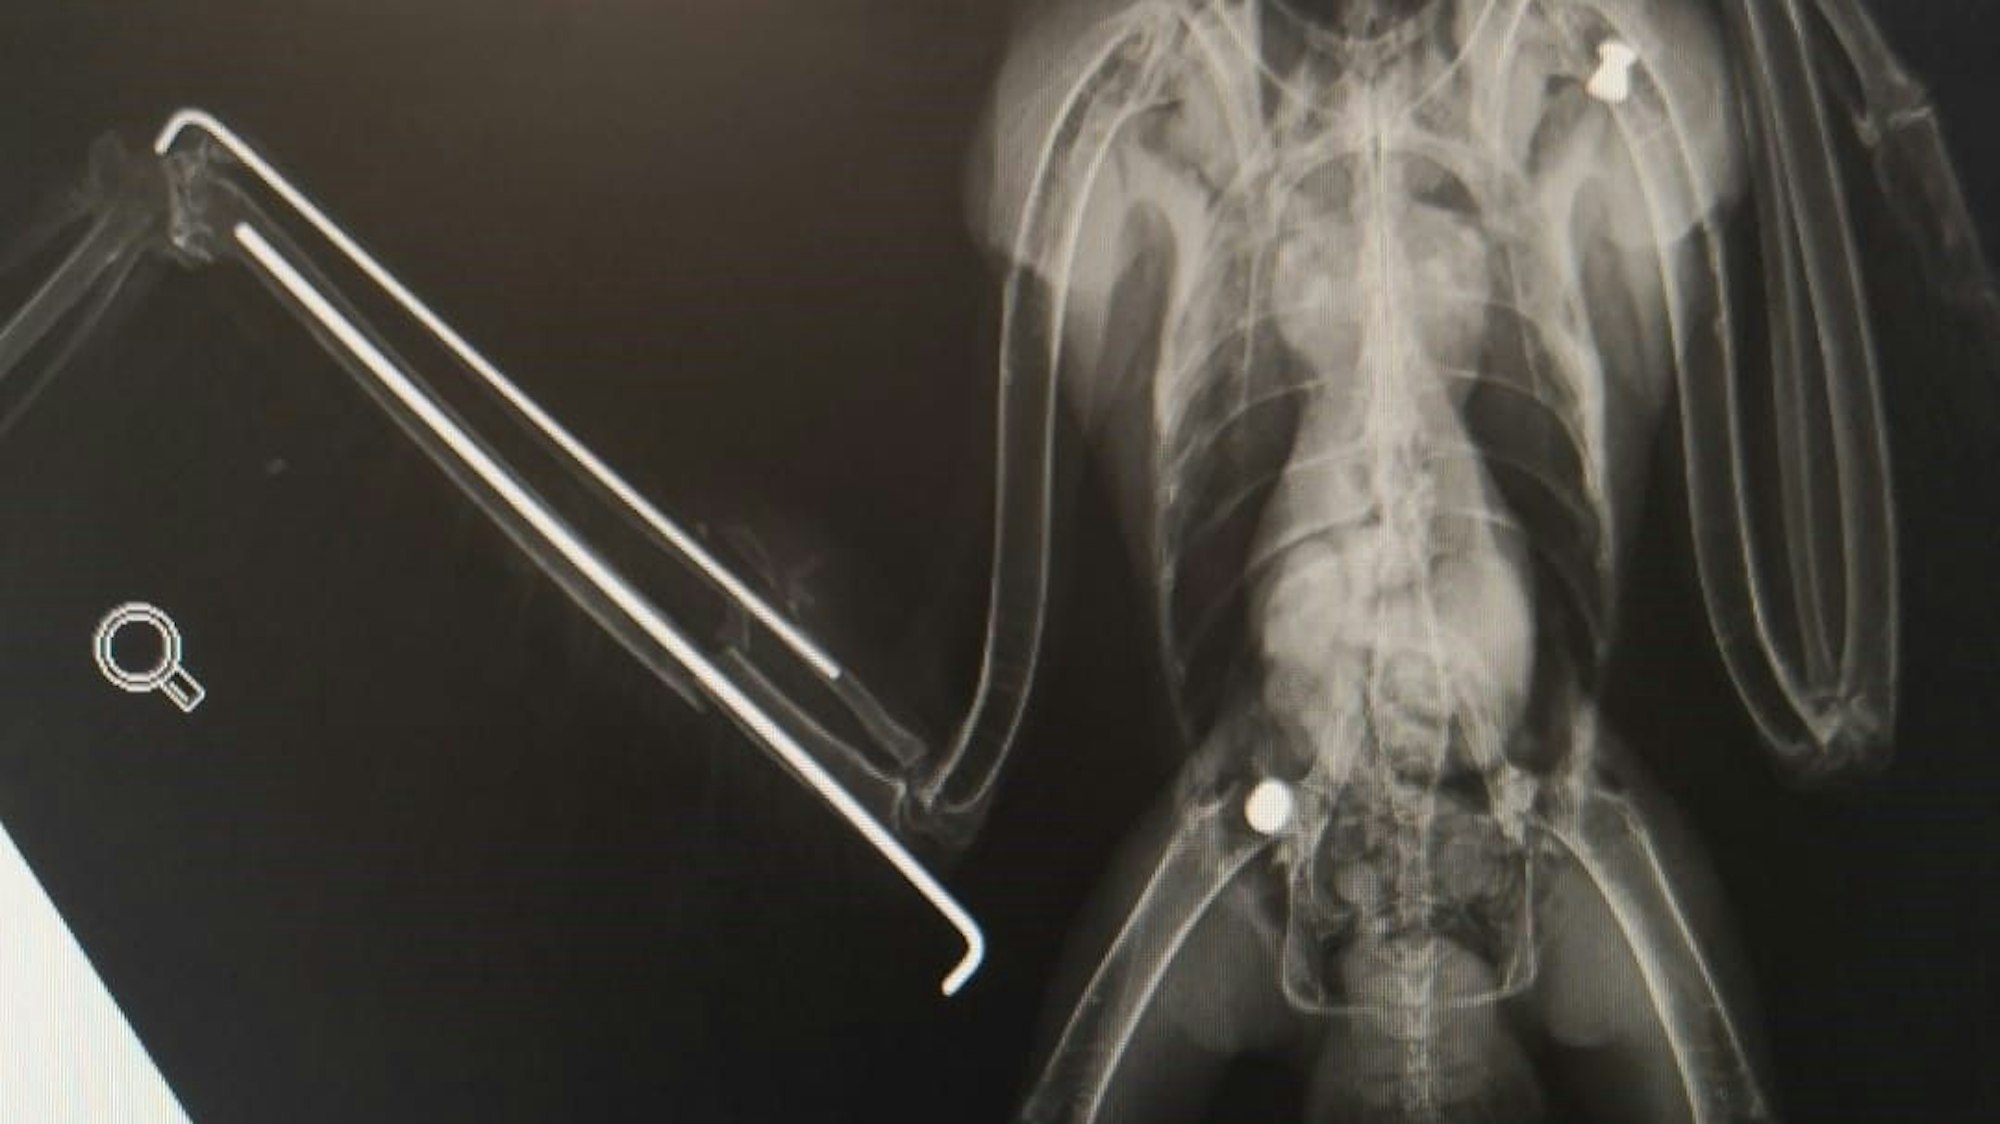

Die Projektile sind im Röntgenbild zu sehen: Dieser Mäusebussard wurde mit einem Luftgewehr abgeschossen und von der Feuerwehr Köln geborgen.

Die Bergische Greifvogelhilfe päppelt den Bussard auf.